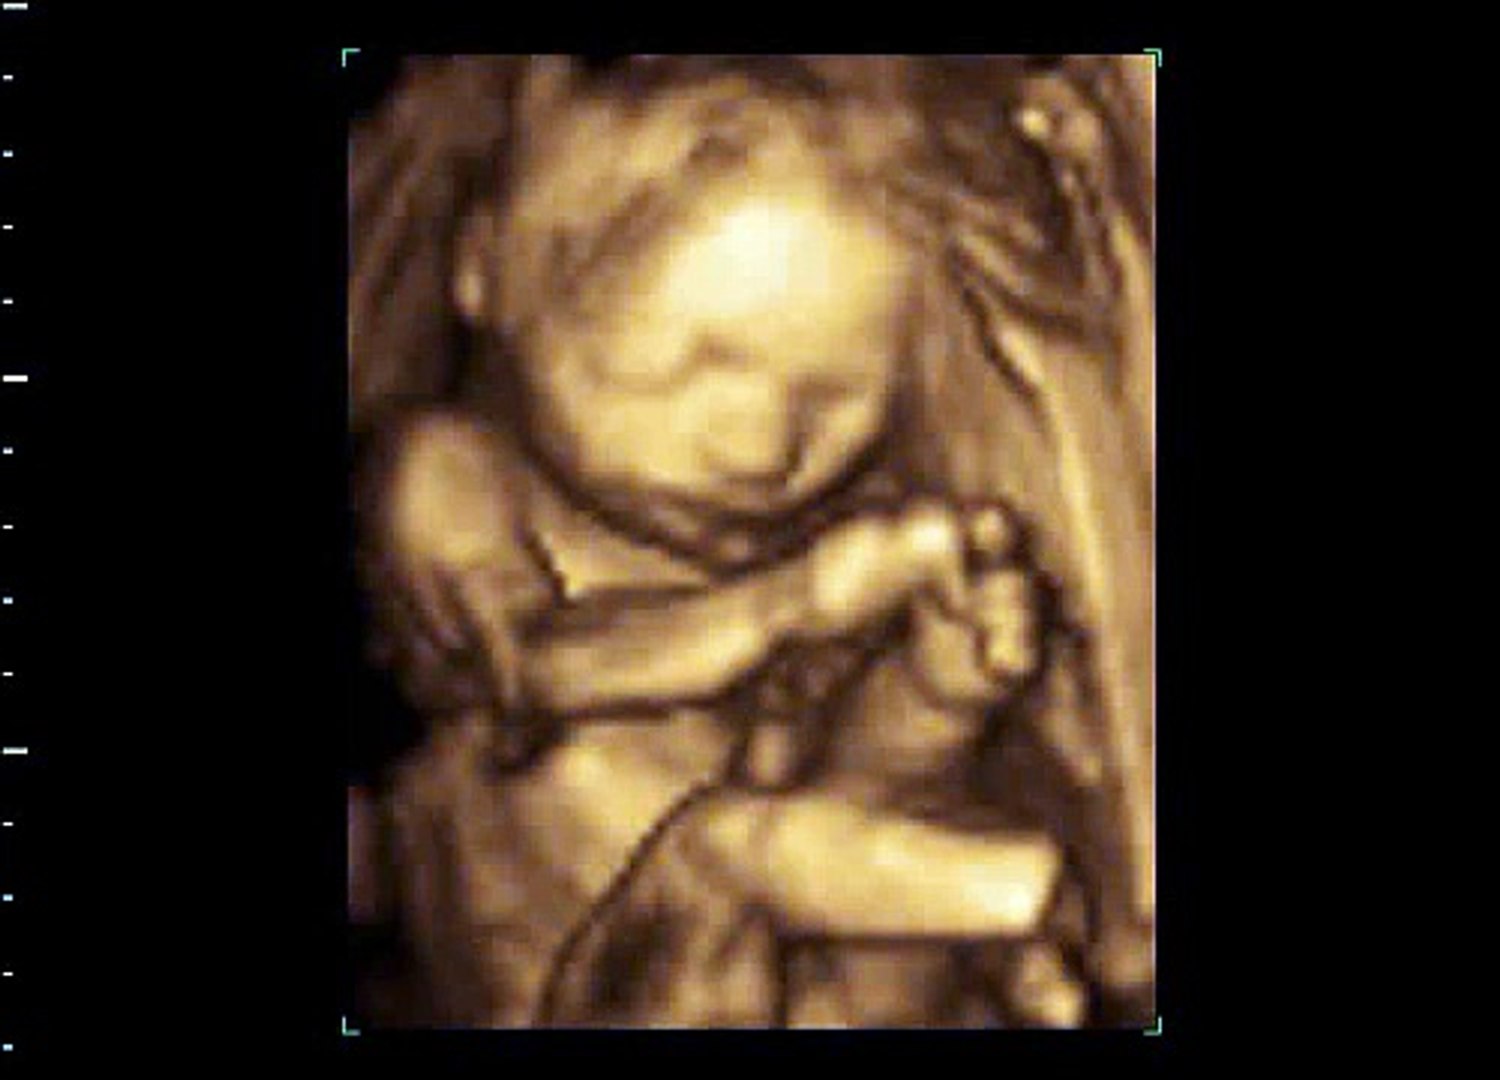

3D Ultrasound Photos at 23 27 Weeks. Measurementsfetal biometry if size discrepancies are present. 23 weeks 3D ultrasound.

The babys height is over 11 inches 289 centimeters from the top of the head to the heel crown-heel length. 3D ultrasound picture of baby at 23 weeks pregnant. When you process to the 23 weeks of pregnancy the BPD is expected to be 58mm which may continue to increase and becomes 94 mm by 38 weeks.

A 3D ultrasound of a human fetus aged 20 weeks 3D ultrasound is a medical ultrasound technique often used in fetal cardiac trans-rectal and intra-vascular applications. 23 weeks 6 days Posted by. FTM and I have been getting really excited and a bit obsessed with seeing my baby.